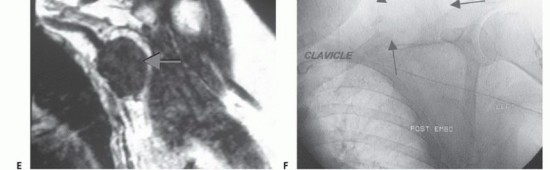

لفهم جراحة استئصال أورام الكتف مع الحفاظ على الطرف، من الضروري أولاً فهم التشريح المعقد لهذه المنطقة. حزام الكتف ليس مجرد مفصل واحد، بل هو منظومة معقدة من العظام، المفاصل، العضلات، الأربطة، الأوتار، الأعصاب، والأوعية الدموية التي تعمل بتناغم لتمكين الذراع من الحركة في جميع الاتجاهات. هذا التعقيد هو ما يجعل جراحة الأورام في هذه المنطقة تحديًا كبيرًا، ويتطلب جراحًا ذا خبرة استثنائية مثل الأستاذ الدكتور محمد هطيف.

* الضفيرة العضدية (Brachial Plexus): شبكة معقدة من الأعصاب التي تنشأ من الرقبة وتمر عبر الإبط، وتغذي جميع عضلات الذراع واليد وتوفر الإحساس. أي إصابة بها يمكن أن تؤدي إلى فقدان كبير للوظيفة.

* الشريان تحت الترقوة والوريد تحت الترقوة: الأوعية الدموية الرئيسية التي تزود الذراع بالدم وتصرفه.

* الأورام الخبيثة الثانوية (النقائل - Metastatic Tumors): تنتشر إلى الكتف من سرطان موجود في جزء آخر من الجسم (مثل الرئة، الثدي، الكلى، البروستاتا، الغدة الدرقية). هذه هي الأورام السرطانية الأكثر شيوعًا في العظام بشكل عام.